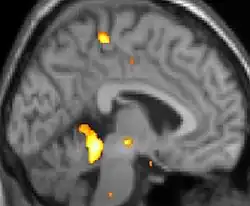

| Positron emission tomography (PET) shows brain areas being activated during pain. | ||

Positron emission tomography (PET) scans indicate the brain areas which are activated during attack only, compared to pain free periods. These pictures show brain areas that are active during pain in yellow/orange color (called "pain matrix"). The area in the center (in all three views) is activated only during cluster headaches. The bottom row voxel-based morphometry shows structural brain differences between individuals with and without CH; only a portion of the hypothalamus is different.[36]